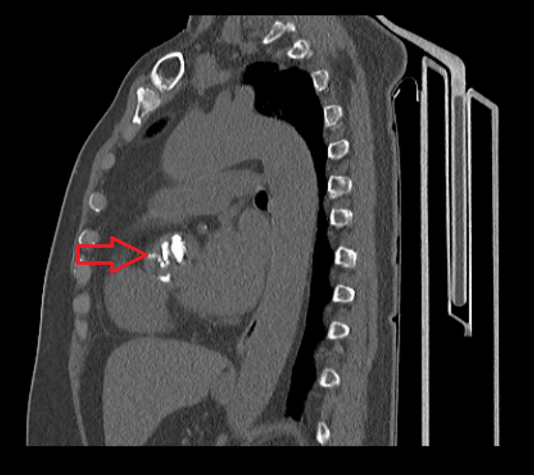

主动脉瓣钙化

ct显示钙化的主动脉瓣

术前ct显示陈女士主动脉瓣严重钙化